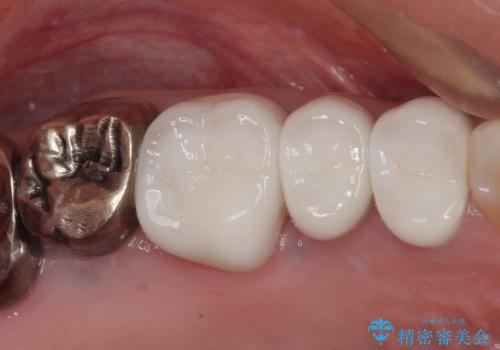

銀歯をセラミックにしたい オールセラミッククラウン

担当医 有澤哲郎

銀歯を外したい オールセラミッククラウン

右下の銀歯が外れた オールセラミッククラウン